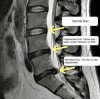

디스크가 튀어나와 신경을 누르고 있는 상황은 누구나 시각적으로 MRI에서 볼 수 있습니다.

하지만 그 외의 근육, 인대, 후관절, 천장관절, 엉덩이 근육의 상태는 의사가 직접 만져보고 눌러보는 이학적 검진 없이는 알 수가 없습니다.